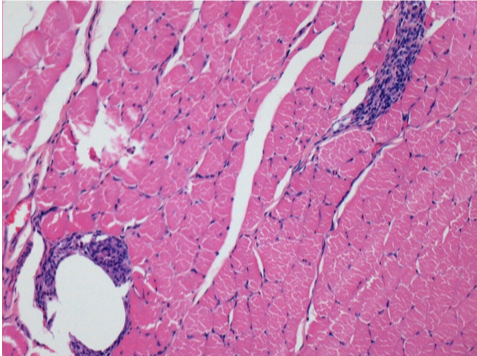

بعد 10 أيام من حقن إندوبيل

10 أيام بعد حقن إندوبيل 0.1 مل في العضلة أمام الظنبوب الأيمن.

هنا قد ترى تشكيل الفجوات التي تحيط بها الخلايا اللمفاوية. الفجوات تختلف عن نخر الأنسجة. يرتبط وجود الخلايا اللمفاوية بنفاذية أغشية الخلايا.

L : Control-100xD10

R:100xD10

R :200xD10

R :400xD10